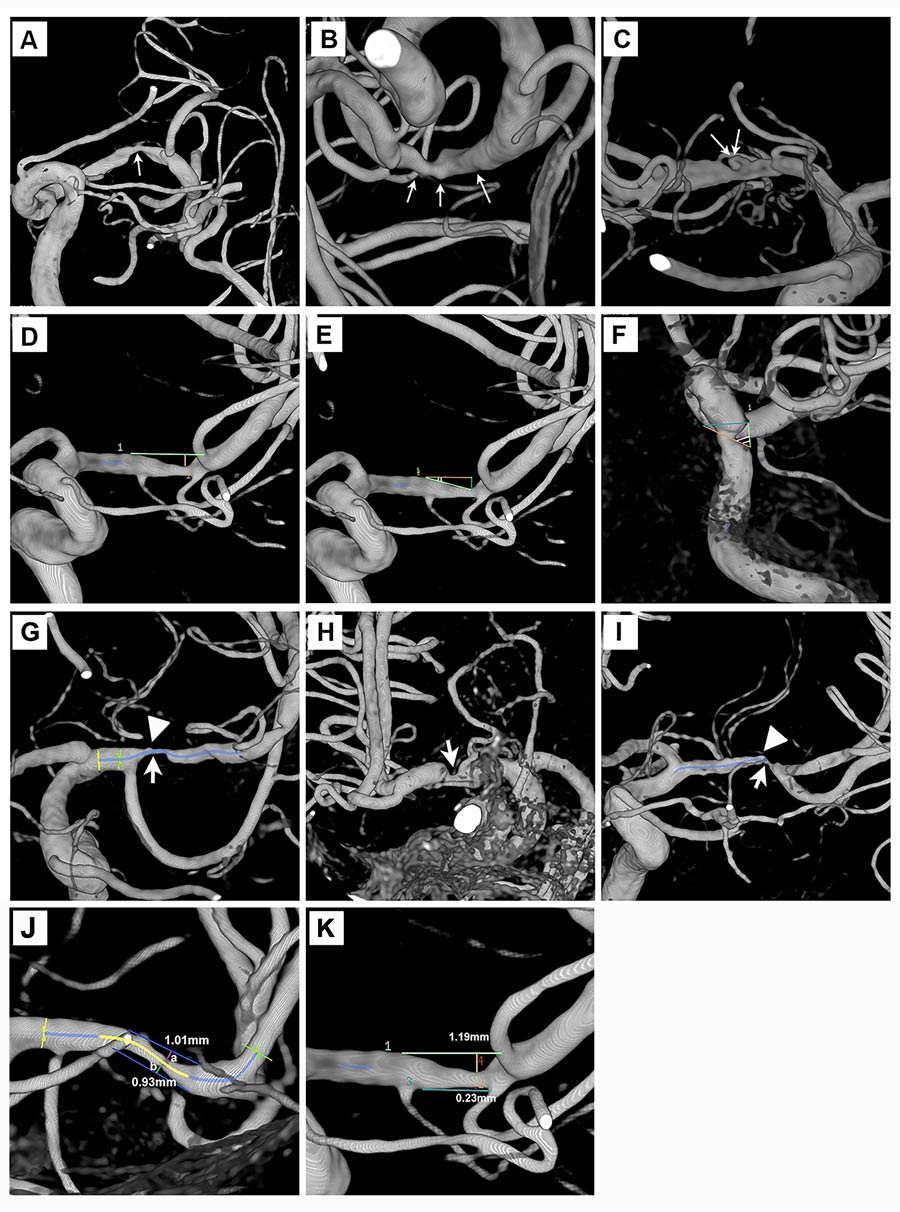

然后研究研究组决定研究ICAD中的斑块形态。这是重要的,因为ICAD斑块形态在很大程度上无表明,与与心脏病发作相关的冠状动脉斑块等其他条件不同。理解斑块的形态,然后可以解释为什么与其他中风机制相比,动脉对动脉栓塞和低血量症更容易引起又一次中风。从本质上讲,小组想知道斑块形态类型是否是造成行程机制的原因。招募了180名中风患者,研究了一种优越的成像技术,称为三维旋转血管造影,其赋予优异的空间分辨率。

梁义教授,余博博士能够在ICAD中识别不同的斑块形态,并将它们与下游梗塞载荷相关联。

梁教授、余教授和冷博士能够识别不同的斑块形态,并将它们与下游脑缺血损伤负荷联系起来。主要形态类型为光滑型、不规则型和溃疡型。溃疡的形态与重复性中风的高发生率有关。溃疡斑块较厚,且与相邻分支动脉粥样硬化病的存在更相关,相邻分支动脉粥样硬化病同时存在脑深部动脉阻塞。然而,需要进一步的纵向研究来确定为什么溃疡斑块是最危险的。本研究收集的信息可用于鉴别溃疡斑块患者。这些患者可以得到更密切的监测,并接受更专业的治疗,以防止第二次中风。